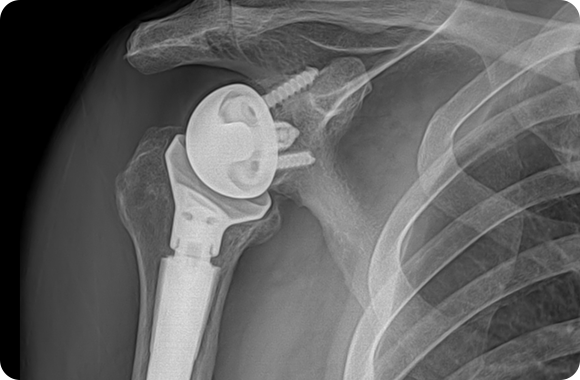

역행성 어깨인공관절치환술 X-ray